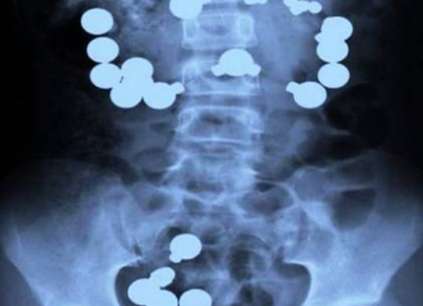

导语:x光片被广泛用于医学治疗当中,为人们检查病症提供了很好的帮助,能更快达到确诊目的。可是你们知道进行x光片检查后,你肯定想不到有结婚戒指、手机等等这些奇怪的东西。接下来呢就由小编为大家揭秘x光片发现十大最恐怖的东西,看完大家就知道爱惜自己的身体啦!

x光片发现十大最恐怖的东西

5、鹅卵石

由于某种原因,中国的一个女孩吞下了20多块鹅卵石,因为她对男友认为瞎吃和喝最终会结束他们的生命感到不高兴,结果是她错了。